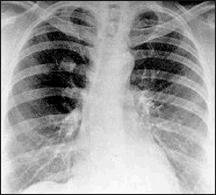

The most potentially widely available and sensitive new imaging modality for the evaluation of SPNs is CT contrast enhancement (Fig 3). The test involves a thin-section density assessment of uncalcified lung nodules before and after the administration of a conventional iodinated contrast material. Malignant neoplasms enhanced significantly more than granulomas and benign neoplasms. The benign lesions that showed significant enhancement were hamartomas and active granulomas. The degree of enhancement was related to the amount of central vascular staining in histologic evaluation of surgical specimens. The overall accuracy of 93 percent establishes CT contrast enhancement as an invaluable tool in the evaluation of indeterminate SPNs.

|

| Fig. 3: Thin-section CT scan before (left) and after (right) intravenous contrast injection. The nodule is enhanced 49 Hounsfield units. Resection showed squamous carcinoma. |